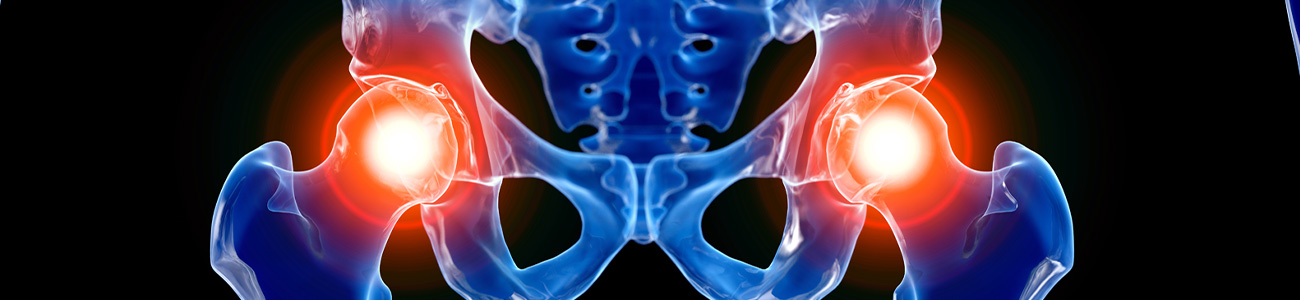

이상근증후군의 원인은 엉덩이 깊숙이 위치한 '이상근'이라는 근육이 과도하게 긴장하거나 비대해져 좌골신경을 압박할 때 발생합니다.

고관절을 둘러싼 근육과 힘줄이 약해지거나 무리하게 사용되면 염증이 생기기 쉽습니다.

특히 오래 서 있거나, 한쪽 다리에 체중을 실는 자세, 다리를 꼬고 앉는 습관, 쪼그려 앉는 동작을 반복하는 경우

고관절에 과도한 부담이 가해져 염증이 유발될 수 있습니다.

또한, 고관절의 불균형이 요추 디스크 탈출(허리디스크)에도 영향을 줄 수 있으며, 염증이 지속되면 야간 통증으로 인해 숙면이 어려워질 수 있습니다.